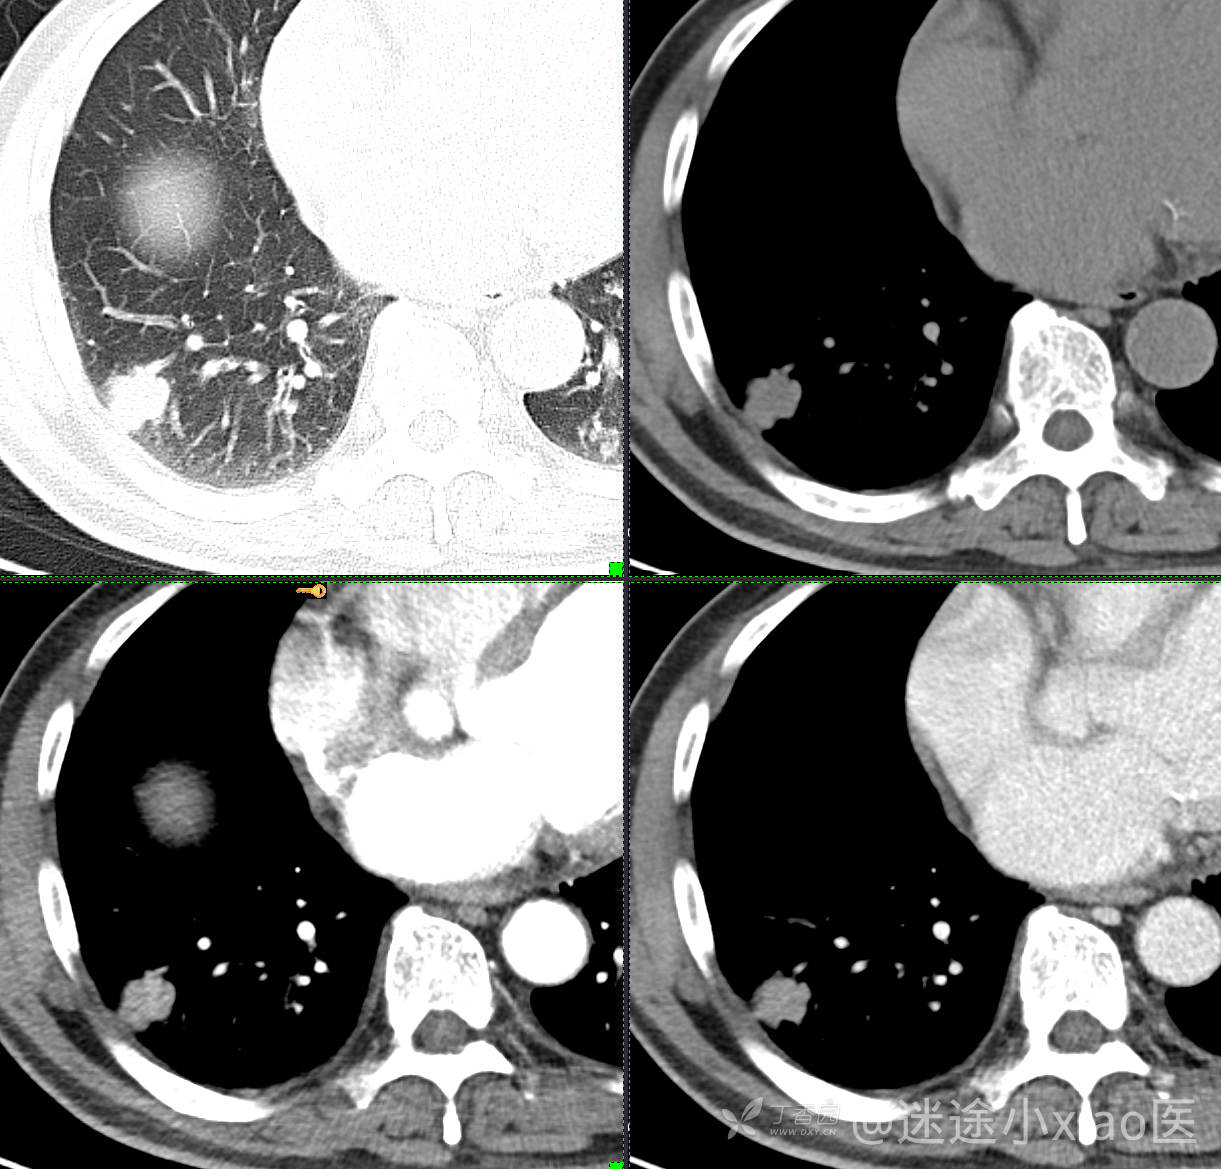

胸组50:老年男性,发现肺占位一天,(结果公布)

主诉: 发现右肺占位1天

现病史: 患者诉1日前在当地医院检查时胸部CT示;肺结节(具体不详),当时无胸闷气急。 无咳嗽咳痰,无胸痛,无恶心呕吐等。今为求进一步治疗,门诊拟“肺结节”收治入院。病来,患者神志清,精神可,胃纳睡眠可,二便无殊,体重无明显增减。